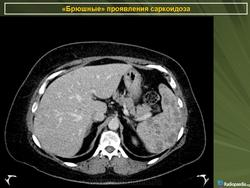

Саркоидоз 3. Брюшной саркоидоз. +

Саркоидоз селезёнки.

Саркоидоз селезенки и печени